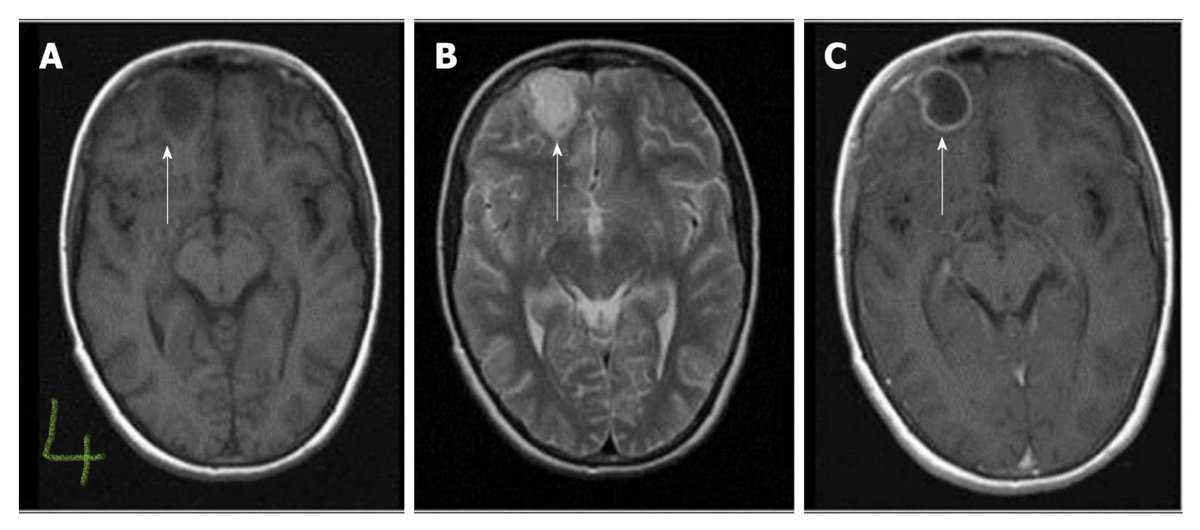

White matter hyperintensities:

HIV encephalopathy bilateral perventricular symmetrical lesion, isointense in T1, no Gd enhancement.

Progressive multifocal leukoencephalopathy asymmetrical perventricular lesion, peripheral DWI restriction, hypointense in T1, may Gd enhancement. ImageImage